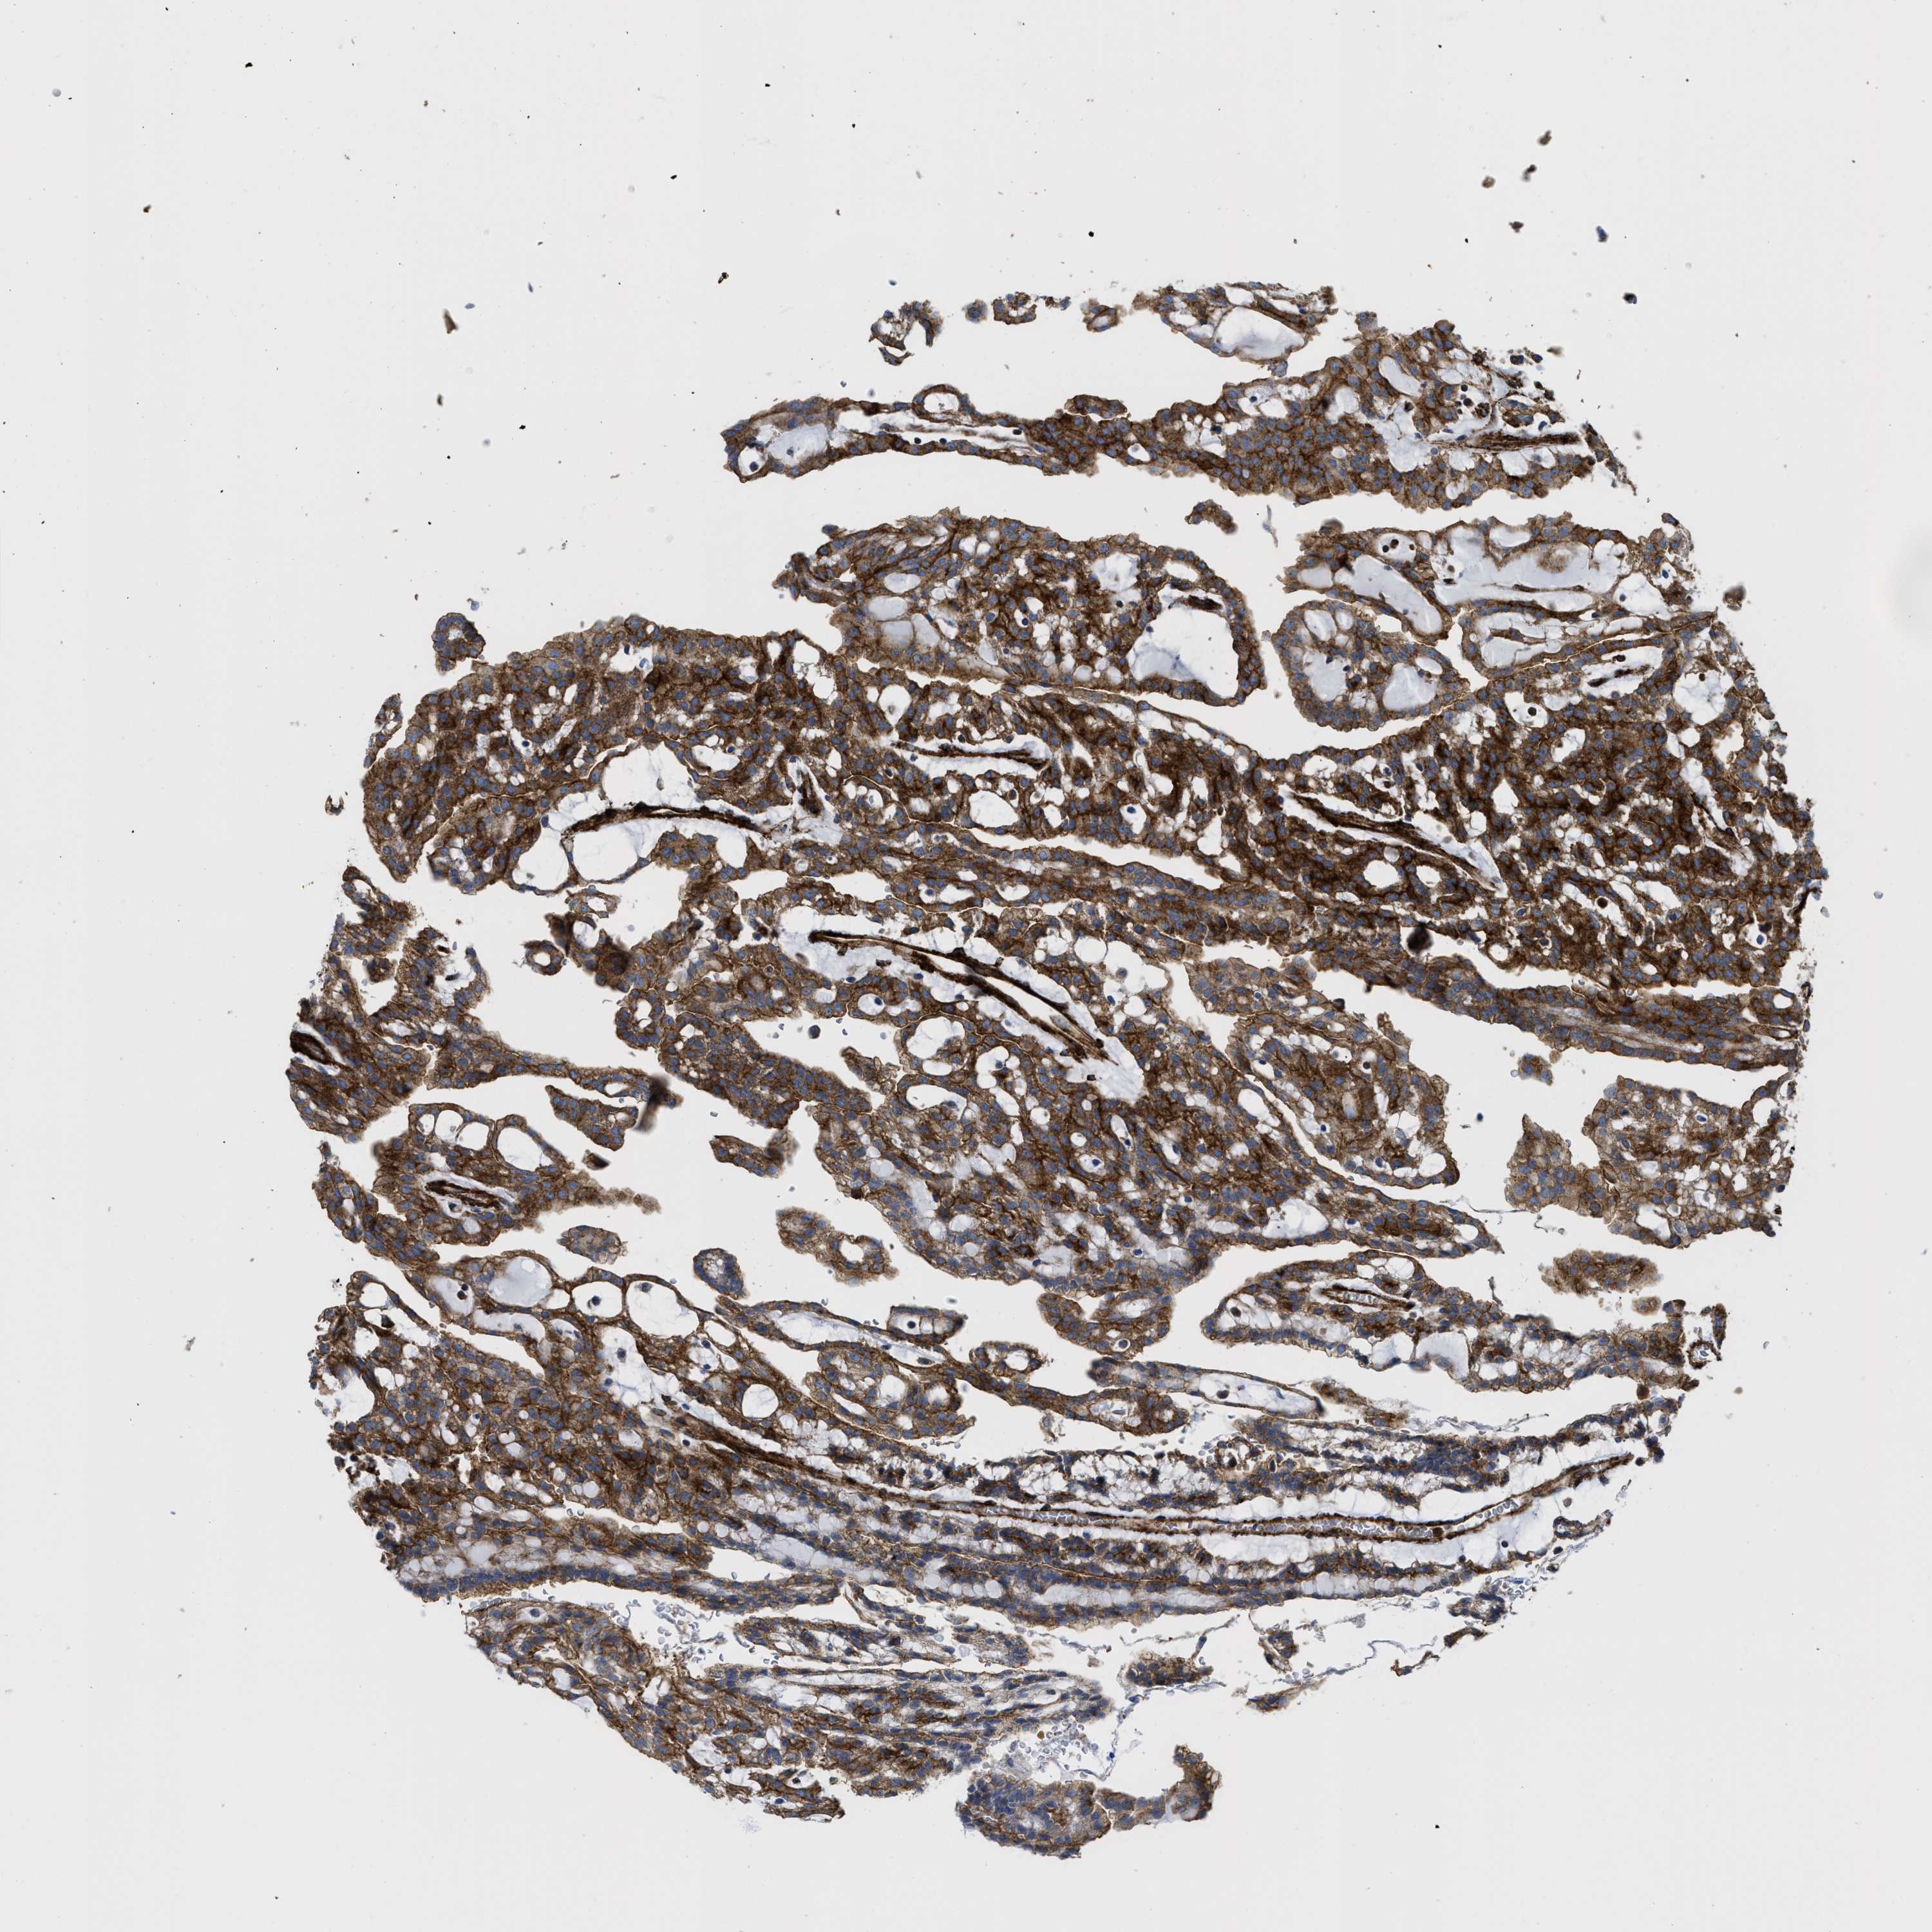

KIDNEY RENAL CLEAR CELL CARCINOMA (VALIDATION) - Interactive survival scatter ploti

The Survival Scatter plot shows the clinical status (i.e. dead or alive) for all individuals in the patient cohort, based on the same data that underlies the corresponding Kaplan-Meier plots. Patients that are alive at last time for follow-up are shown in blue and patients who have died during the study are shown in red.

The x-axis shows the expression levels (FPKM) of the investigated gene in the tumor tissue at the time of diagnosis. The y-axis shows the follow-up time after diagnosis (years). Both axes are complimented with kernel density curves demonstrating the data density over the axes. The top density plot shows the expression levels (FPKM) distribution among dead (red) and alive patients (blue). The right density plot shows the data density of the survived years of dead patients with high and low expression levels respectively, stratified using the cutoff indicated by the vertical dashed line through the Survival Scatter plot. This cutoff is automatically defined based on the FPKM cutoff that minimizes the p-score. The cutoff can be changed by dragging the vertical line or by entering a cutoff value in the square labeled "Current cut-off".

Under the Survival Scatter plot the p-score landscape (black curve; left axis) is shown together with dead median separation (red curve; right axis). Dead median separation is the difference in median mRNA expression between patients who have died with high and low expression, respectively. It is calculated as follows: median FPKM expression of dead patients with high expression - median FPKM expression of dead patients with low expression. This is intended to aid the user in visually exploring custom cutoffs and the associated p-scores and dead median separation.

Individual patient data is displayed and can be filtered by clicking on one or more of the category buttons on the top of the page. Categories describing expression level and patient information include: high, low, alive, dead, female, male and tumor stages. The scale of the x-axis can be toggled between linear and log-scale by clicking on the "x log" button. Mouse-over function shows TCGA ID, patient information and mRNA expression (FPKM) for each patient.

& Survival analysisi

Kaplan-Meier plots summarize results from analysis of correlation between mRNA expression level and patient survival. Patients were divided based on level of expression into one of the two groups "low" (under cut off) or "high" (over cut off). X-axis shows time for survival (years) and y-axis shows the probability of survival, where 1.0 corresponds to 100 percent.

HIP1 is validated prognostic, high expression is favorable in Kidney Renal Clear Cell Carcinoma (validation)

Best expression cut offi

Based on the FPKM value of each gene, patients were classified into two groups and association between prognosis (survival) and gene expression (FPKM) was examined. The best expression cut-off refers the FPKM value that yields maximal difference with regard to survival between the two groups at the lowest log-rank P-value. Best expression cut-off was selected based on survival analysis .

When clicking on this number, the vertical dashed line indicating cut-off, the interactive survival plot, and the Kaplan-Meier curve will be adjusted to show results based on the best expression cut-off.

: 19.11

TCGA RNA samplesi

RNA-seq data is reported as average FPKM (number Fragments Per Kilobase of exon per Million reads), generated by the The Cancer Genome Atlas (TCGA) .

Normal distribution across the dataset is visualized with box plots, shown as median and 25th and 75th percentiles. Points are displayed as outliers if they are above or below 1.5 times the interquartile range. FPKM values of the individual samples are presented next to the box plot.

Average pTPM 17.6

Number of samples 100